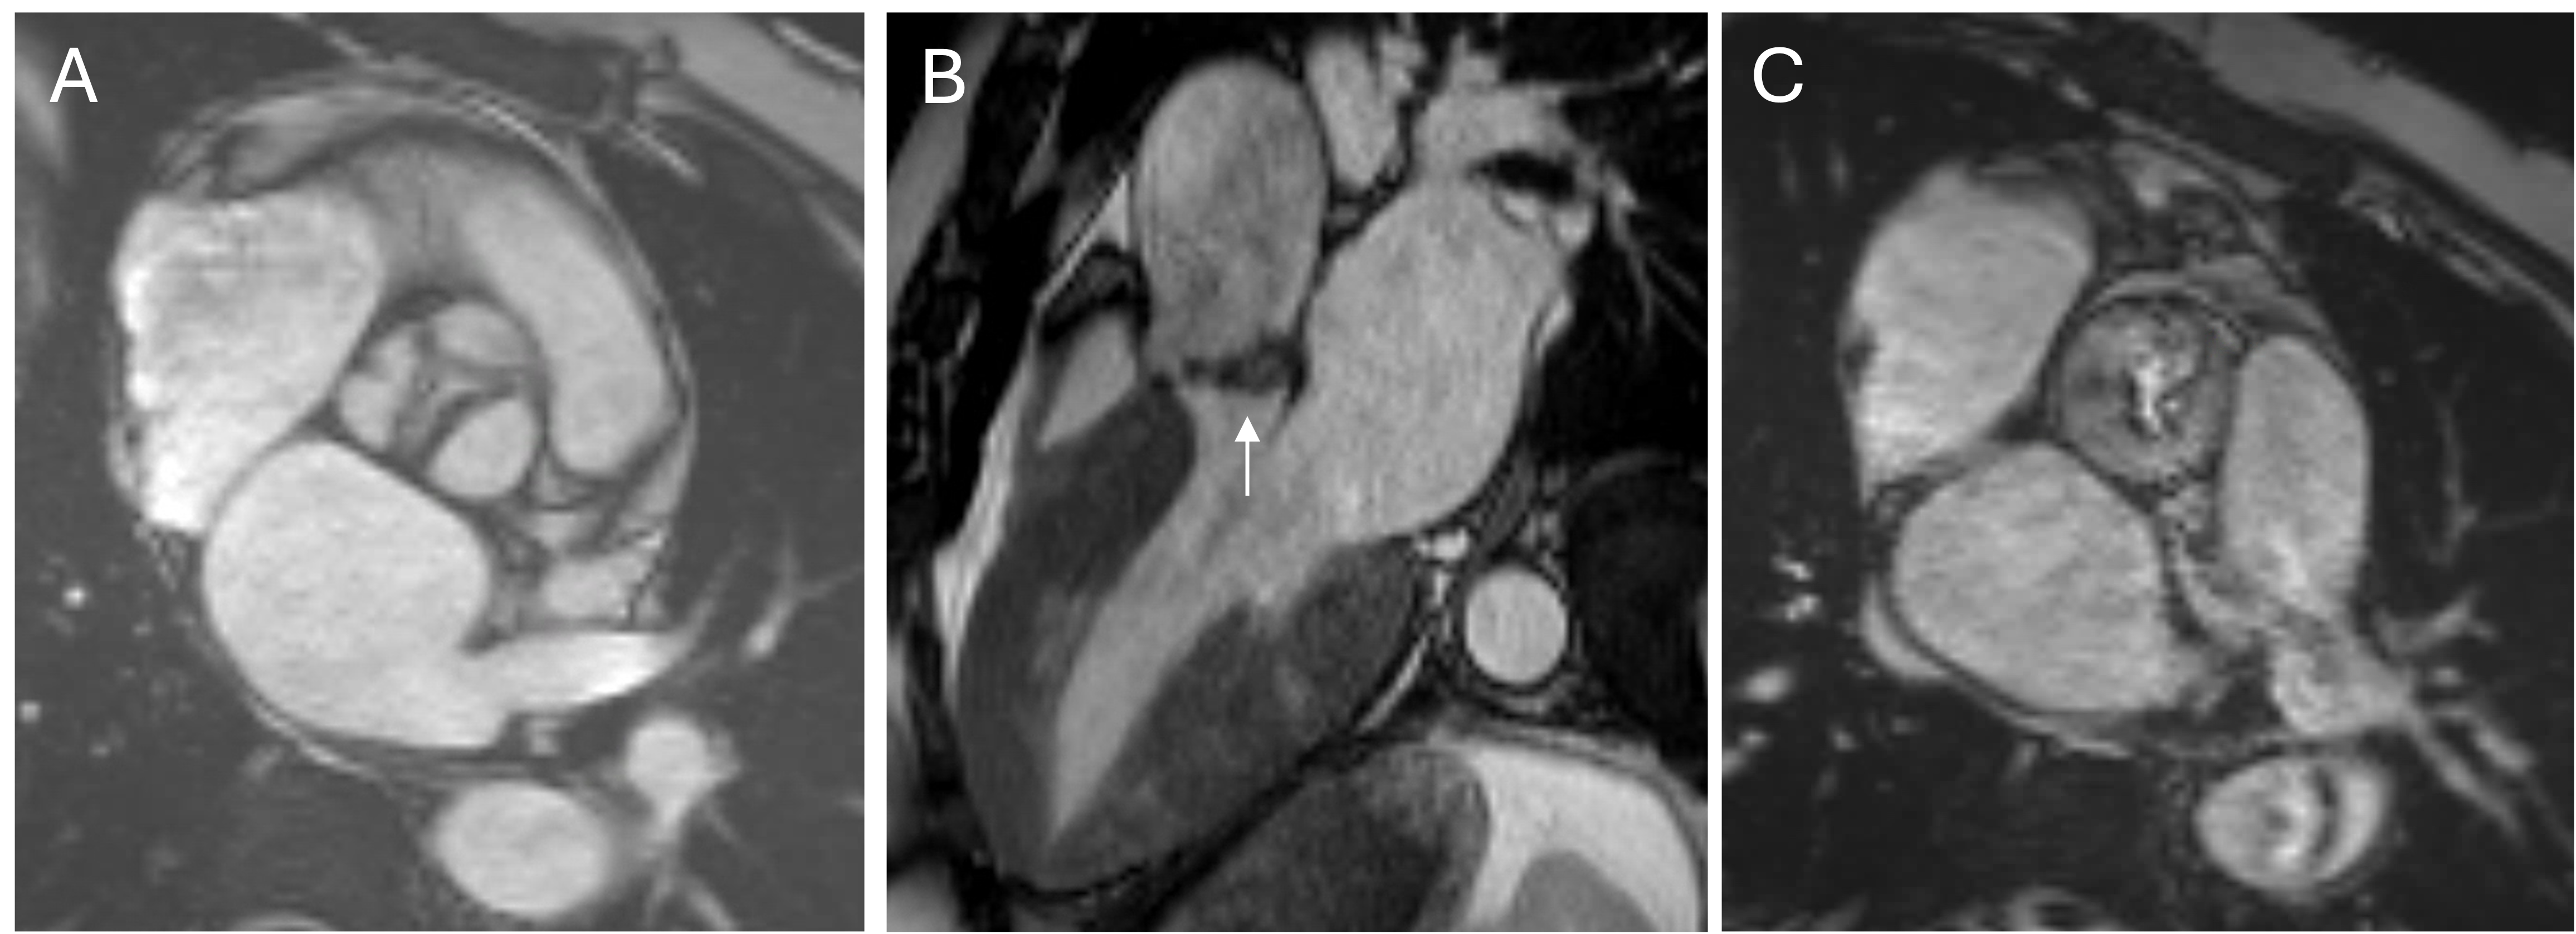

Short axis (A-C) and two-chamber (D) views demonstrating small focal subendocardial infarctions of the basal lateral and inferior walls.